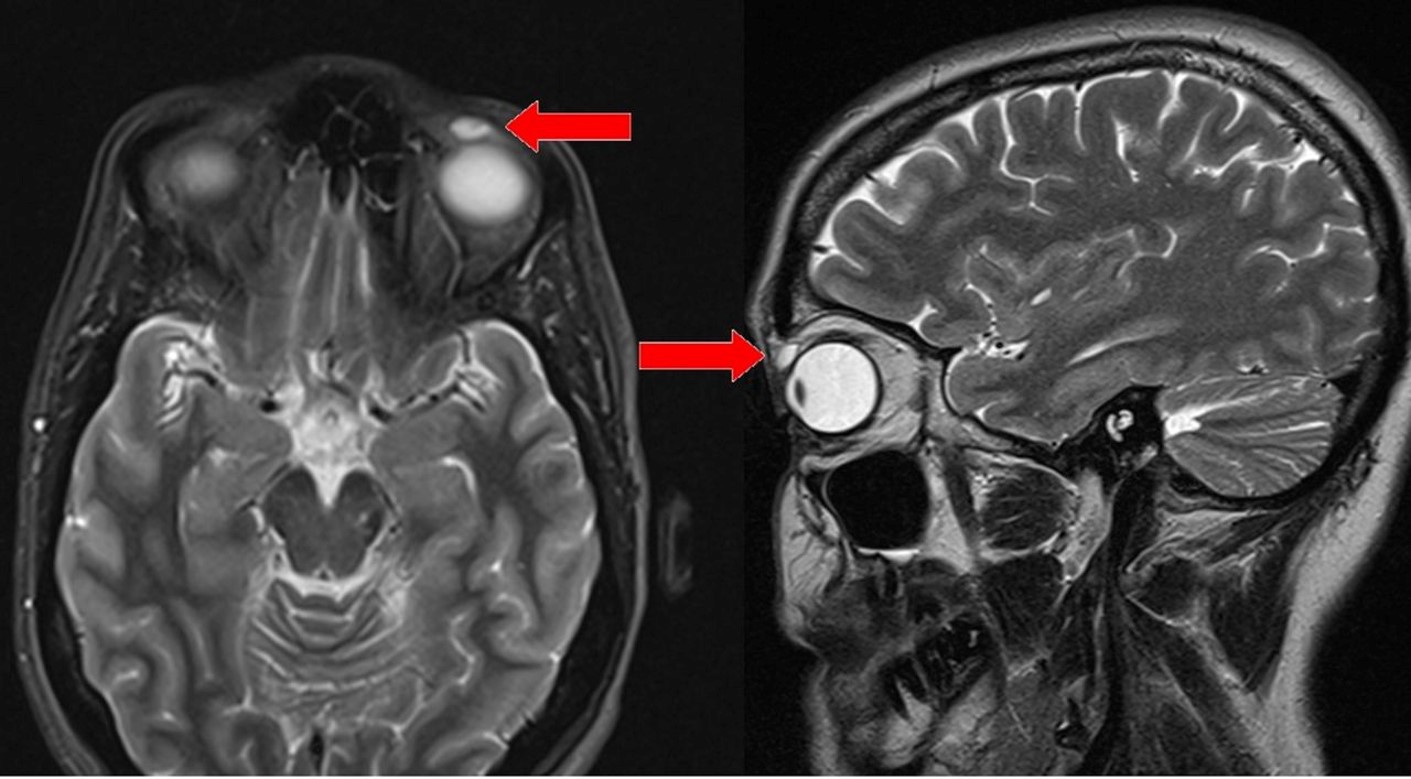

Sau khi thăm khám và chụp MRI, các bác sĩ chuẩn đoán có một khối u nang đường kính 6mm ở trong mắt người phụ nữ này vì vậy họ lên kế hoạch phẫu thuật để loại bỏ nó. Tuy nhiên, đến khi tiến hành mổ mắt bác sĩ mới giật mình thảng thốt vì đó không phải khối u mà là vật thể lạ gì đó. Họ phải hết sức cẩn thận gỡ ra và phát hiện đó chính là một chiếc kính áp tròng.

Ban đầu các bác sĩ còn tưởng là khối u trong mắt người phụ nữ.